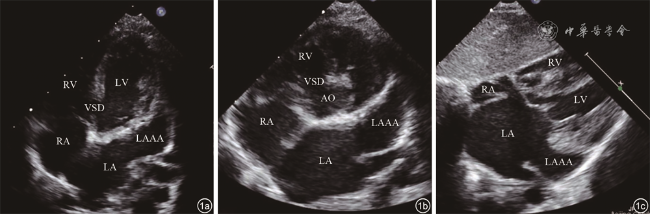

9例患者均经超声心动图检查诊断为LAAA,表现为:(1)四腔心、心底短轴、剑突下等切面二维超声图像可见左心室游离壁外囊状无回声结构,为LAAA;(2)LAAA与左心房交通(图1);(3)彩色多普勒可见LAAA与左心房间血流信号往返(图2);(4)巨大LAAA可压迫左心室或其他毗邻结构(图3);(5)同时可显示合并的其他占位性病变(图4)。

图2 左心耳瘤彩色多普勒超声图像。图示左心耳瘤与左心房交通,其间可见血流信号往返。图a为左心房内血液进入左心耳瘤;图b为左心耳瘤内血液回流入左心房